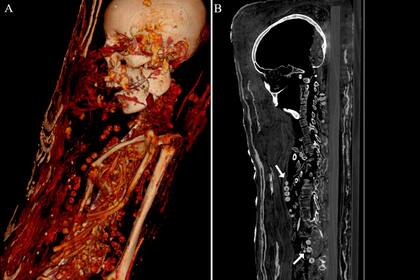

Los escaneos similares a las tomografías computarizadas a los que fueron sometidas las momias revelaron datos sorprendentes. Al menos una de estas tres fue enterrada con sus órganos vitales, incluso el cerebro, y que los cuerpos de las dos mujeres fueron decorados con hermosos collares al momento de la sepultura.

Además de los elementos que acompañaban a las momias, las tomografías computarizadas revelaron distintos problemas médicos, incluida la artritis en la mujer. "El examen de los individuos reveló que eran muy jóvenes al momento de la muerte, sin embargo, no se pudo determinar la causa de la misma", sostuvo Zesch al sitio WordsSideKick.com, declaraciones que reproduce Live Science

El estudio reveló que el hombre murió entre los 25 y los 30 años. Medía 1,64 metros, tenía dos dientes permanentes sin erupcionar y varias caries. Además, algunos de los huesos estaban quebrados y mezclados, probablemente, porque alguien desenvolvió el cuerpo poco después del descubrimiento de la momia.

"Estamos seguros de que no se extrajo el cerebro ni los órganos internos de estas momias. Es muy probable que solo se hayan conservado debido a una especie de deshidratación con el uso de natrón [,mezcla especial para este tipo de procedimientos}, pero no hay una gran cantidad de líquidos de embalsamamiento", precisa Zesch.

Por su parte, la mujer debe haber muerto entre los 30 y los 40 años y medía 1,51 metros. Tenía artritis avanzada en la rodilla izquierda. La adolescente, que llevaba un tocado, de acuerdo con la tomografía computarizada, murió entre los 17 y los 19 años y su estatura era de 1,56 metros. Tenía un tumor benigno en la columna conocido como hemangioma vertebral, que es más común en personas adultas.